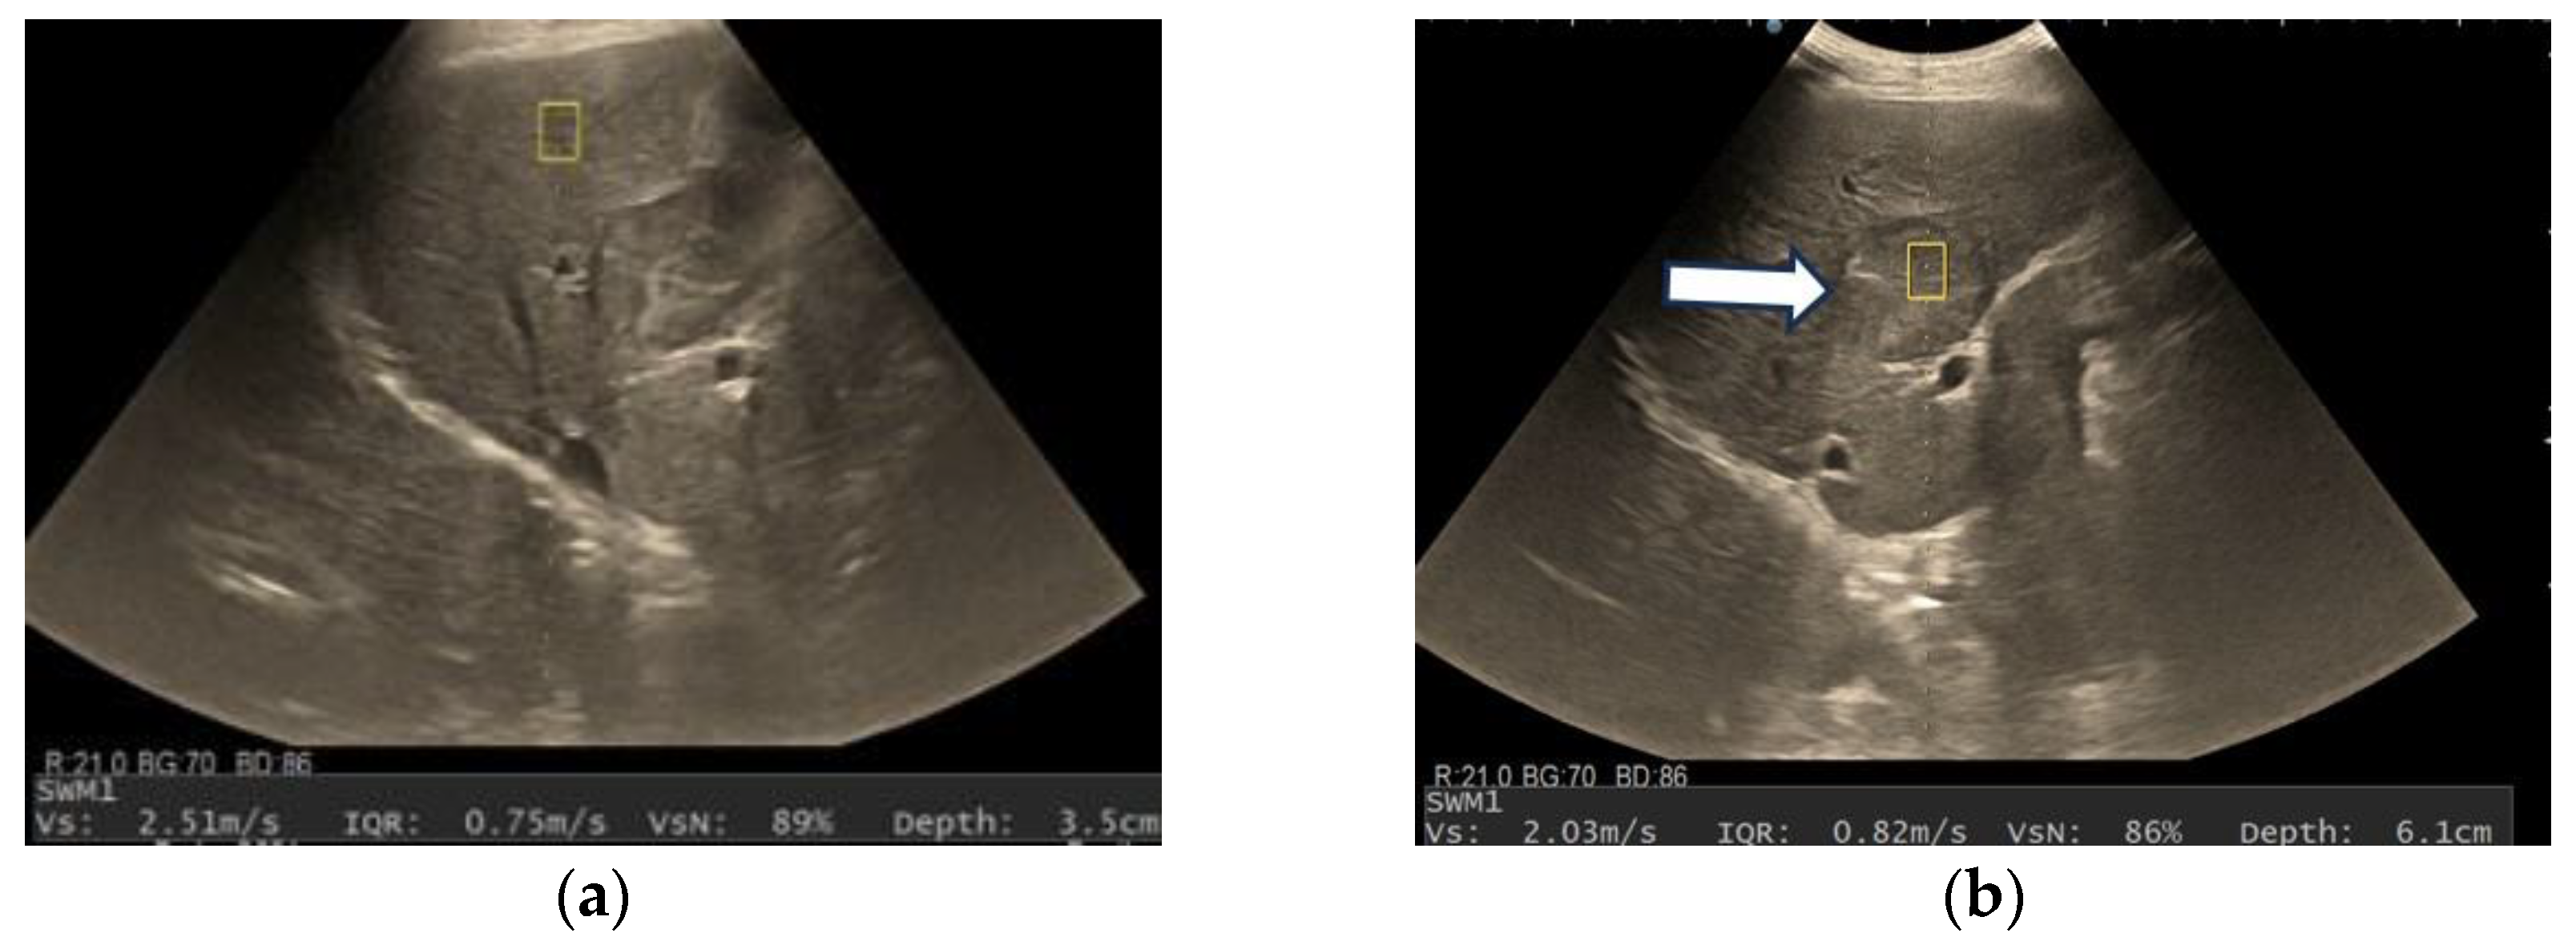

3.3. Shear Wave Measurements in Liver Tumors

| Variables | VsN ≥ 50% | VsN < 50% | p-Value |

|---|---|---|---|

| Vs (m/s) | 1.66 ± 0.3 | 1.73 ± 0.44 | 0.74 |

| Depth of the lesion (cm) | 5.14 ± 1.16 | 5.73 ± 1.60 | 1.31 |

| Size (mm) | 75.59 ± 29.62 | 66.17 ± 45 | 0.06 |

| Presence of liver cirrhosis | 17 | 15 | 0.34 |